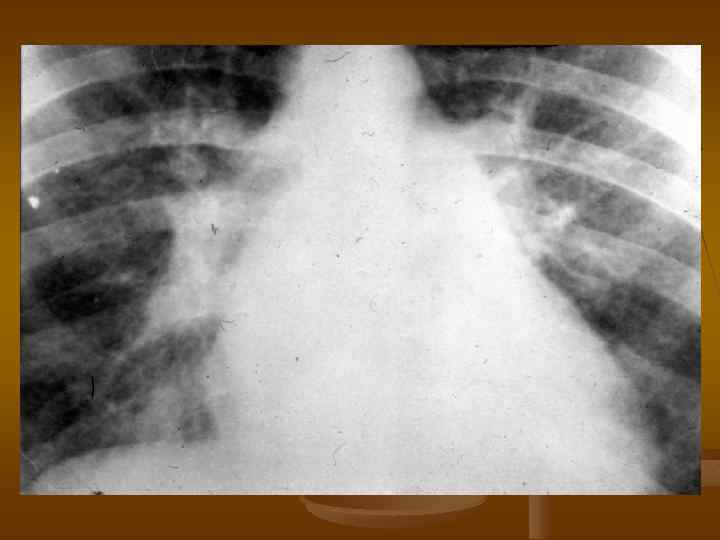

Рентгенограмма грудной клетки больного со стенозом трехстворчатого клапана во второй косой проекции.

Рентгенограмма грудной клетки больного с недостаточностью трехстворчатого клапана во второй косой проекции.